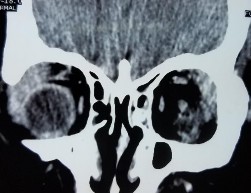

Bệnh nhân nam, 45 tuổi, 2M: sưng nề mi góc ngoài + sờ thấy khối u

Bệnh nhân sờ thấy khối u và sưng nề mi cách vào viện 8 tháng, không đau nhức (A, B). Tiền sử u lympho di căn phổi 1 năm đang điều trị. Hình ảnh cắt lớp vi tính toàn bộ hai tuyến lệ là khối tăng tỉ trọng, bờ đều, kích thước u MP 13 x 30 mm, MT 24 x 30mm, khối u đúc khuôn quanh nhãn cầu (C, D). Kết quả giải phẫu bệnh là u lympho ác tính (u lympho ác tính) (E: HE x 200, F: HE x 400). Bệnh nhân được điều trị bằng hóa trị.